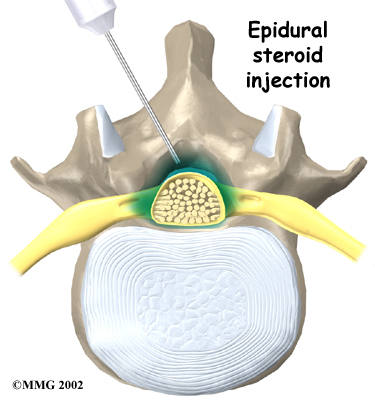

Some patients who continue to have symptoms are given an (ESI). Steroids are powerful anti-inflammatories, meaning they reduce pain and swelling. In an ESI, medication is injected into the space around the lumbar nerve roots. This area is called the epidural space. Some doctors inject only a steroid. Most doctors, however, combine a steroid with a long-lasting numbing medication. Generally, an ESI is given only when other treatments aren't working. But ESIs are not always successful in relieving pain. If they do work, they may only provide temporary relief.